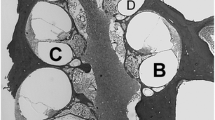

The estimated region of electrode B was selected as the region for histological analysis to ensure that we analyzed the cochlea in a region that was directly adjacent to the electrode array. Before removing the cochlear implant, a small notch in the bone was made with a needle to indicate where electrode B was located. Two implants (animals 335 and 361) were accidentally removed during the ear extraction process so their B location was estimated and based on the average distance from the round window to the B electrode for the subjects with intact implants. The implanted cochleae were removed, and tissue processing was performed as previously described (Yagi et al. 2000) and then modified as described below. Each cochlea was locally perfused with the glutaraldehyde and cacodylate buffer solution and placed in 3% ethylenediaminetetraacetic acid (EDTA) solution to decalcify until sufficiently soft for sectioning (approximately 1–2 months). Once decalcified, the implant was removed, and the cochlea was embedded in JB-4 resin (Electron Microscopy Scientific, Washington, PA, USA). Sections were obtained in the para-midmodiolar plane (Kanzaki et al. 2002) and were centered at the location of the notch in the bone that indicated the location of electrode B. These para-midmodiolar sections provided six measurable profiles of Rosenthal’s canal (Fig. 2). Sections were cut at a thickness of 3 μm, and 40 sections were obtained and collected on glass slides, covering a length of 120 μm along the cochlea spiral. The sections were stained with 1% toluidine blue in 1% sodium borate.

Light micrograph of a para-midmodiolar section from animal 350 showing areas of histological analysis. The letter designations are in the scala vestibuli, where resin from the sectioning procedure remains in most profiles and in scala tympani in profile “c”. While an imperfect section, it includes the entire cochlea showing regions that were analyzed and those that were not. Profile “a” represented the basal-most profile where the hair cells and neural elements were adjacent to the electrode array. Fibrous tissue remains in the scala tympani in profile “a” where the implant resided. Scale bar (upper left) represents 80 μm.

We sought to analyze regions of the cochlea adjacent to as well as apical to the electrode array. Thus, we analyzed four profiles of the cochlea and labeled them a, b, c, and d, starting from the basal end of the cochlea (Fig. 2). Profile “a” was the region upon which the para-midmodiolar sections were centered and represents the approximated region occupied by electrode B. Profile “a” is distinct from the remaining three profiles, as profile “a” was the only region analyzed that was adjacent to the electrode array. In contrast, the remaining three profiles (profiles b, c, and d) were apical to the electrode array. Regions apical to profile “d” were difficult to analyze because Rosenthal’s canal was not well defined. For the remainder of the manuscript, we consider profile “a” to be synonymous with the analyzed region of the cochlea that was adjacent to the electrode array, specifically the 120-μm region that was centered on the approximated location of electrode B.